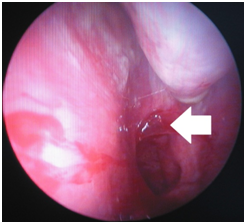

All the patients underwent endoscopic excision under anaesthesia. After the administration of local anaesthesia, the mass was excised using nasal endoscope, and its base was cauterized to control bleeding (Figure 6) (Figure 7). The patient's postoperative course was uneventful.

Figure 7 Picture showing site of attachment of the mass [arrow] at the choana..